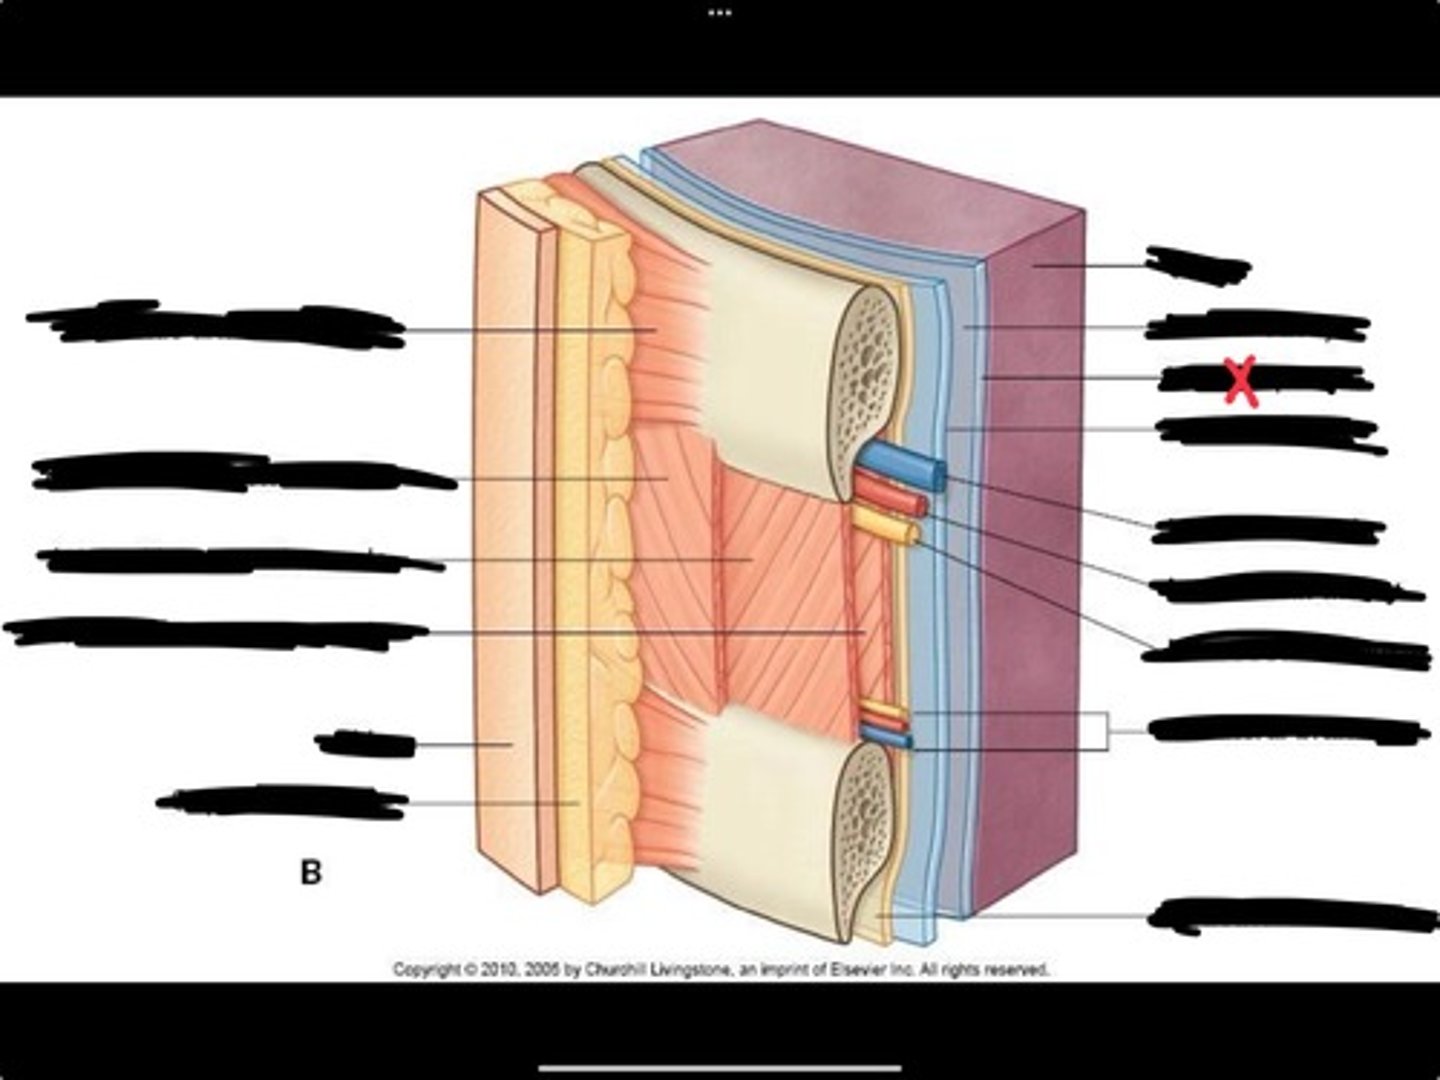

Innermost intercostal muscle

Skin

Internal intercostal muscle

External intercostal muscle

Serratus anterior muscle

Lung

Pleural cavity

Visceral pleura

Parietal cavity

Intercostal vein

Intercostal artery

Collateral branches

Intercostal nerve

Endothoracic fascia